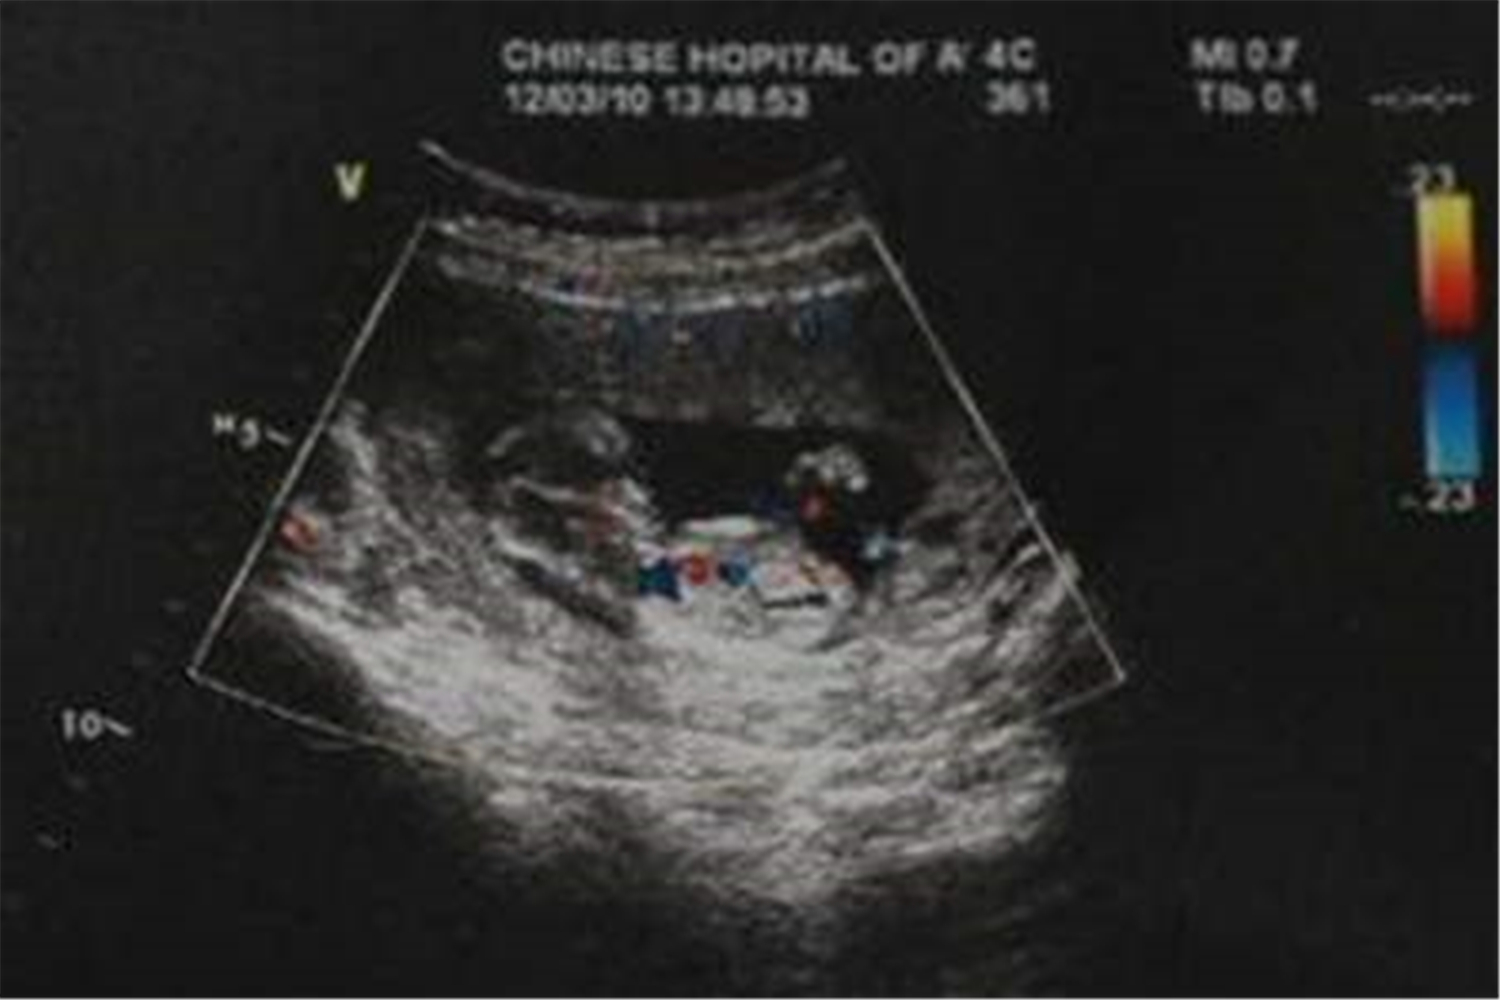

NT的中文翻译是颈项透明层,检查的是胎宝宝脖颈、后背皮肤层和筋膜中间组织厚度的最大层,主要反映的是皮肤下淋巴液的汇聚程度。

简单来说,NT筛查是胎儿排畸的第一道防线,是用来筛查是否存在唐氏综合征的。

它和B超不同,监控重点是胎宝妊娠前期染色体发生病变的可能情况,有利于及时发现和预防畸形,孕妈可不要错过。